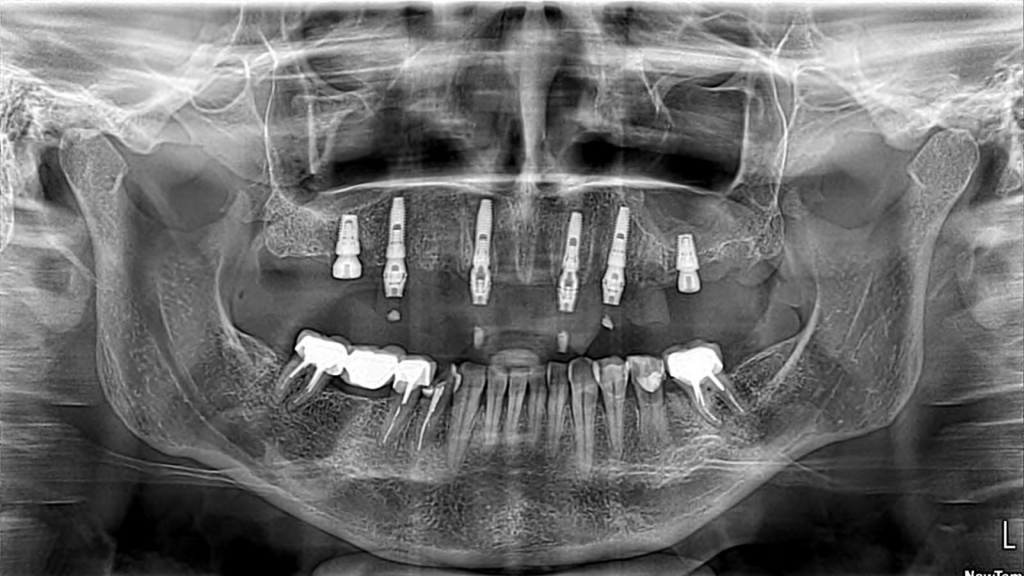

Описание клинического случая:

- Атравматичное удаление оставшихся зубов на верхней челюсти

- Одномоментная установка дентальных имплантатов, система Impro

- Костная пластика с применением костного материала аллоплант

- Одноэтапная фиксация мультиюнит-абатмента

- Снятие слепков (силикон А — Improviser)

- Наложение швов шовным материалом Glycolon 5.0

- Фиксация фрезерованных временных коронок